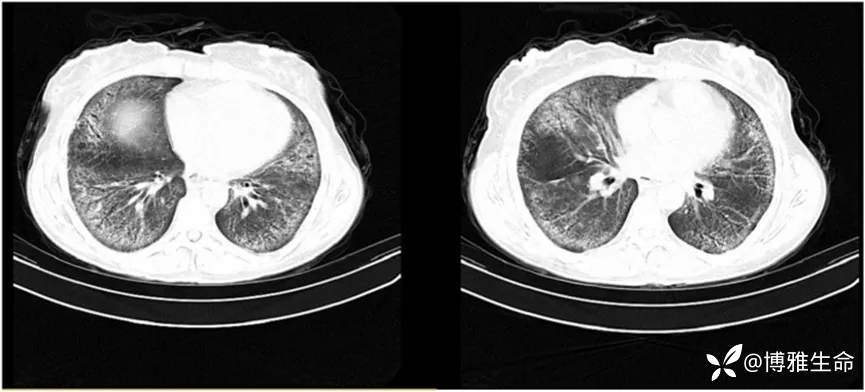

在第一个疗程后约两个月复查胸部CT,结果显示毛玻璃样实变和纤维化改变明显减少(如下图)。肺功能检查没有显示出显著的变化(预计FEV 1值= 47%,预计FVC = 44%,FEV 1/FVC = 111%)。体格检查显示肺部湿罗音减少。目前,该患者仍在接受后续随访。

图片来自文献[1]